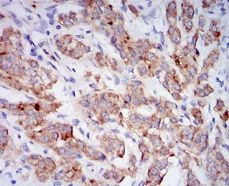

CD10 Mouse Monoclonal antibody[7D4B1]

This gene encodes a common acute lymphocytic leukemia antigen that is an important cell surface marker in the diagnosis of human acute lymphocytic leukemia (ALL). This protein is present on leukemic cells of pre-B phenotype, which represent 85% of cases of ALL. This protein is not restricted to leukemic cells, however, and is found on a variety of normal tissues. It is a glycoprotein that is particularly abundant in kidney, where it is present on the brush border of proximal tubules and on glomerular epithelium. The protein is a neutral endopeptidase that cleaves peptides at the amino side of hydrophobic residues and inactivates several peptide hormones including glucagon, enkephalins, substance P, neurotensin, oxytocin, and bradykinin. This gene, which encodes a 100-kD type II transmembrane glycoprotein, exists in a single copy of greater than 45 kb. The 5' untranslated region of this gene is alternatively spliced, resulting in four separate mRNA transcripts. The coding region is not affected by alternative splicing.

Immunogen:    Purified recombinant fragment of human CD10 (AA: 52-246) expressed in E. Coli.

IHC    1/200 - 1/1000